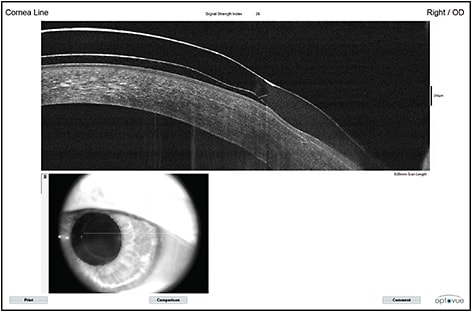

Fitting Problems Some patients will complain of fluctuating vision and/or discomfort that, on the surface, do not appear to be a vault problem (e.g., lenses are comfortable on some days and uncomfortable on others). Close inspection of optical coherence tomography (OCT) images has identified a potential problem that is remedied by altering the application technique.

If a patient (or office staff) is applying UltraHealth lenses too forcefully, by pushing the lens onto the eye, excessive fluid will be forced from the bowl of the lens, and a vacuum will be created in the post-lens tear reservoir. This will, in turn, pull the lens too tightly onto the cornea and force the inner landing zone to indent the cornea. Remedy this problem by teaching the patient to allow the fluid in the lens to pull the lens onto the cornea during application. This “gentle” application technique prevents the vacuum of fluid, and the visual fluctuations and comfort problems will stop (Figure 8).

Figure 8a. An UltraHealth lens forcefully applied on a keratoconic eye. The inner landing zone is severely compressing the cornea. This patient complained of odd visual fluctuations and admitted to strongly forcing the lens onto the eye (in an attempt to avoid application bubbles).

Figure 8b. The same lens after removal and reapplication with the “gentle” technique. The corneal area under the inner landing zone is still compressed from the weeks of warpage. However, there is now ample space under the inner landing zone. This patient practiced the “gentle” technique for several days and reported that his vision had completely stabilized.

If this does not fix the problem, it is likely that you are overvaulting the cornea and placing too much pressure on the inner landing zone. Decrease the vault by 50μm, and this problem will resolve.